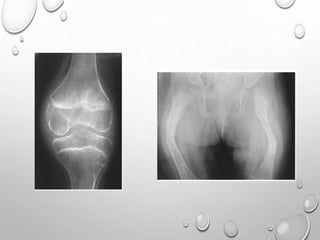

EPIPHYSEAL DYSPLASIA

MULTIPLEX

AD TRANSMISSION

EQUAL IN MALES AND FEMALES

FIRST NOTICED WHEN CHILD BEGINS TO WALK , WITH COMMON

COMPLAINTS OF WADDLING GAIT , DIFFICULTY RUNNING.

MILDER CASES MAY NOT APPARENT UNTIL EARLY ADULTHOOD ,

WHEN PREMATURE JOINT DEGENERATIVE CHANGES OCCURS.

PATHOPHYSIOLOGY : ABNORMALITY OF EPIPHYSEAL

CHONDROCYTES ( NO DECREASED , ABNORMAL ARRANGEMENT

)….LEADING TO DELAYED AND DISORDERLY OSSIFICATION F

EPIPHYSES.

LL >> UL

SHORT STATURE WITH TENDENCY TOWARDS DWARFISM

BILATERAL SYMMETRICAL INVOLVEMENT

DEVELOPMENT OF EPIPHYSES DELAYED

APPEARANCE IS MOTTLED WITH IRREGULAR MINERALIZATION

FLATTENED AND SQUARED-OFF EPIPHYSES

DOUBLE LAYERED PATELLA……PATHOGNMONIC

HYPOPLASTIC TIBIAL AND FEMORAL CONDYLES WITH SHALLOW

INTERCONDYLAR NOTCH

METAPHYSES ARE FLARED

CARPALS , TARSALS AND LONG TUBULAR BONES OF HAND ,SOMETIMES

FEET ARE SHORT AND THICK

SPINE : ANTERIOR WEDGING , SCOLIOSIS

IRREGULAR EPIPHYSES LEADS TO PREMATURE AND SEVERE

DEGENERATIVE CHANGE ESPECIALLY IN KNEES AND HIPS.